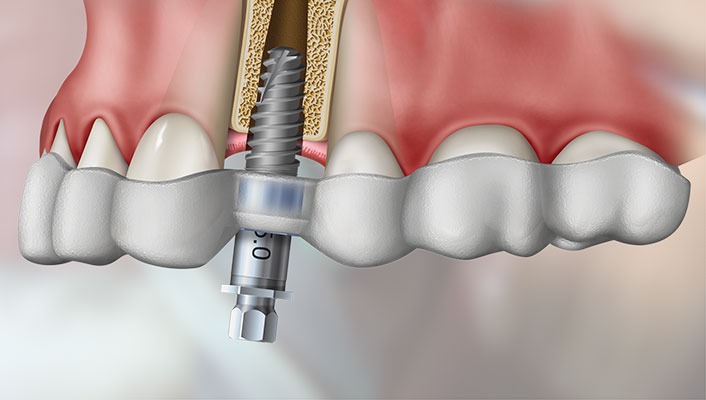

Implantodontia

Precisão milimétrica com planejamento 3D.

Prótese Protocolo sobre Implante

Reabilitações totais fixas sobre implante, devolvendo estética, função mastigatória e, principalmente, confiança e autoestima.